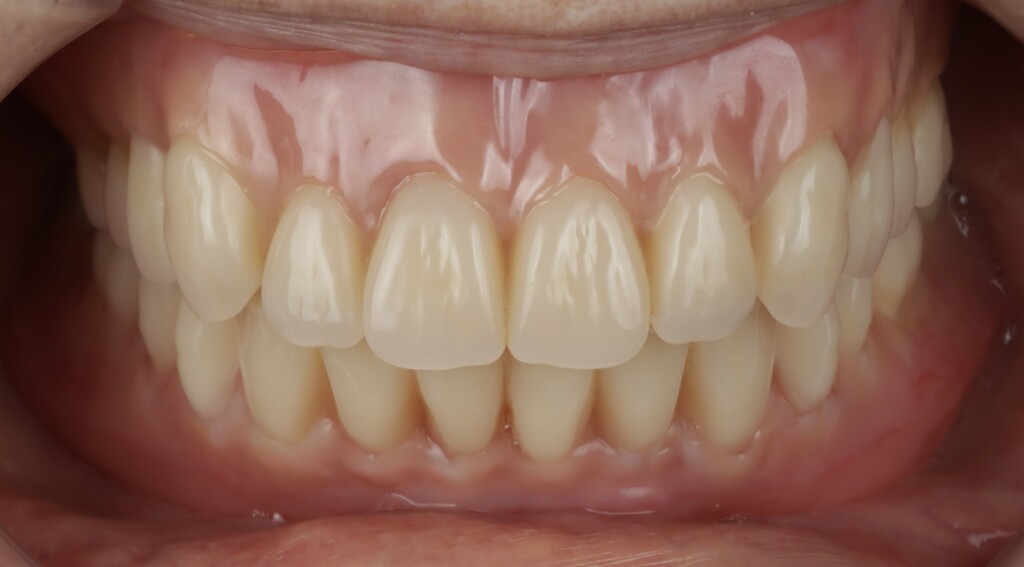

Before/After

治療前

最終精密義歯

治療後

歯肉の質感まで再現された最終精密義歯

天然歯と見分けがつかない最終精密義歯